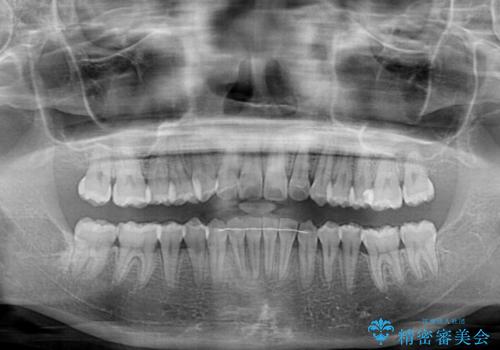

前歯のデコボコと隠れてしまう下顎前歯 インビザラインですっきりと改善

- 前歯のデコボコと、深い咬み合わせにより前歯が隠れていることを気にして来院された患者様です。

海外に長期滞在する予定があるとのことで、インビザラインにて矯正治療を行うこととしました。

インビザライン発注後に長期滞在先から2年間ほど帰国することができず、インビザラインの有効期限内に終了できるのか不安でしたが、矯正治療開始後は十分な装着時間を達成され、1年未満の期間で無事に終えることができました。